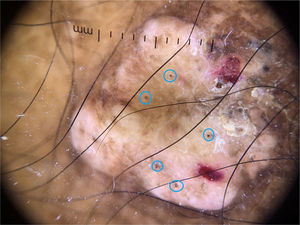

Não há descrição na literatura da dermatoscopia de lesões de lobomicose. Demonstramos os achados de uma dermatoscopia de lesão nodular da perna deste paciente, com áreas de hiperpigmentação entremeadas por hipopigmentação, escamas, crostas hemáticas e vários pontos pretos. Estruturas vasculares não foram evidenciadas (fig. 4).